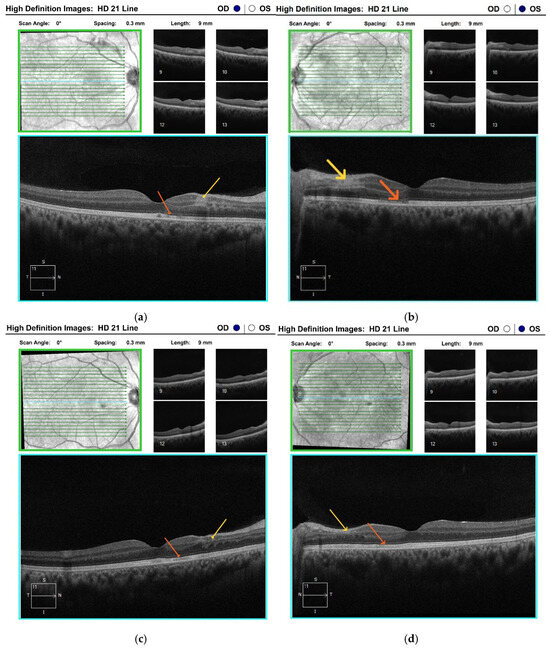

Optical coherence tomography (OCT) of the maculae revealed alterations in both the inner and outer retinal layers, with more pronounced changes in the left eye (Figure 3a,b).

Figure 3.

Optical coherence tomography of the maculae of both eyes: (a,b) at the time of diagnosis of Purtscher-like retinopathy—reveals thickening, hyperreflectivity, and loss of definition of the inner retinal layers, corresponding to ischaemic areas and Purtscher flecken (yellow arrow); in the outer retinal layers, a paramacular, nasal disruption of the photoreceptor layer (orange arrow) is observed, more pronounced in the left eye (b); (c,d) two months after follow-up—the paramacular, hyperreflective areas in the inner retinal layers demonstrate atrophy and thinning in the affected zones (yellow arrow); in the outer layers, partial restoration of the ellipsoid zone is seen, with persistent disruption of the line corresponding to the junction between the inner and outer segments of the photoreceptors (orange arrow); (e,f) nearly two years after follow-up—no progression of findings in either eye (yellow and orange arrows). HD 21 Line scan, line length 9 mm, scan angle 0°, inter-line spacing 0.3 mm. Scan volume: 9 × 6 × 2 mm. Horizontal scale ≈ 8.8 µm/pixel; vertical scale ≈ 1.95 µm/pixel; inter-line scale = 0.3 mm.

Two months following the initial examination, the patient’s visual acuity was 6/6 in both eyes. Haemorrhages, cotton-wool spots and Purtscher fleckens had fully resolved in the right eye and were almost completely resorbed in the left (Figure 1e,f). On OCT, the paramacular hyperreflective areas in the inner retinal layers had progressed to atrophy and thinning in the affected regions. Partial restoration of the ellipsoid zone was observed in the outer retinal layers (Figure 3c,d). Follow-up computerised perimetry demonstrated a reduction in areas of decreased light sensitivity (Figure 6c,d).

Over an almost two-year follow-up period, the patient’s visual acuity remained at 6/6, with no progression observed in the OCT findings (Figure 3e,f).

Optical coherence tomography in our patient at the onset of the disease revealed thickening, hyperreflectivity, and loss of definition in the inner retinal layers—indicative of ischaemia of the inner retinal circulation. Nevertheless, OCT-A demonstrated preserved perfusion in the superficial plexus, whereas small areas of capillary hypoperfusion and a slight nasal enlargement of the foveal avascular zone in the left eye were observed in the deep plexus. Similar OCT findings have been reported by other authors in patients with Purtscher-like retinopathy, emphasising that OCT-A can effectively replace invasive FFA for the detection of retinal ischaemic alterations, even at an early stage [22]. In our case, microischaemic alterations in the deep plexus were not visualised on FFA.

Macular atrophy and disruption of the IS/OS junction, as observed on OCT, are considered unfavourable prognostic indicators [6,22]. Although IS/OS junction alterations were also observed in our patient, central visual acuity in both eyes was fully restored, as the lesions were located outside the fovea. Alaei et al. describe an intriguing case of pancreatitis-induced Purtscher-like retinopathy in a pregnant woman following excessive use of gastric acid-suppressing medications. During follow-up, they identified an OCT finding similar to ours—reduced retinal thickness in the outer layers due to photoreceptor injury [23]. According to the authors, the final functional outcome of the condition ranges from complete recovery to permanent visual loss, underscoring the importance of early detection and prompt initiation of therapy. Nevertheless, there is currently a lack of compelling evidence supporting the efficacy of any of the treatments employed [6].